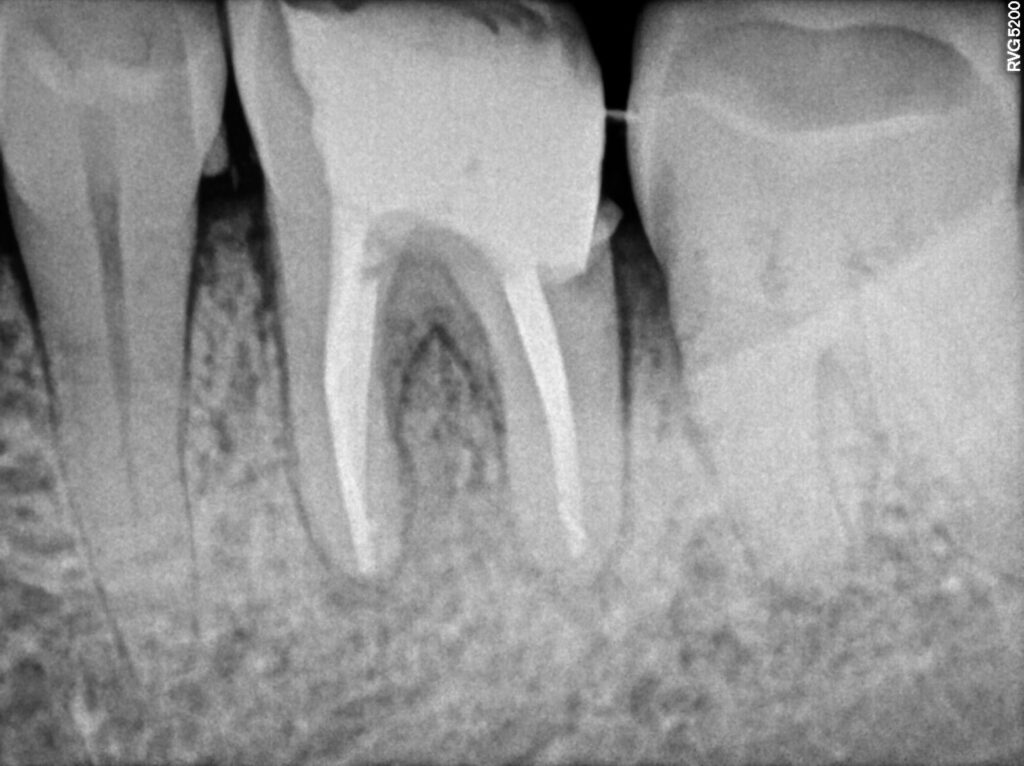

2. Re-Root Canal Treatment at Microdent Dentistry Pune

Re-Root Canal Treatment

Patient Background: Dentist accidentally broke the fine ( instrument ) in one root .. Patient was referred to our practice for re treatment of root canal and retrieval of seperated instrument.

First visit :- Instrument retrieval.. referral case ..

instrument retrieval done successfully and dressing given

Second visit :- pre obturation x ray taken and dressing given with calcium hydroxide

Third visit :- obturation of canals and root canal treatment completed .